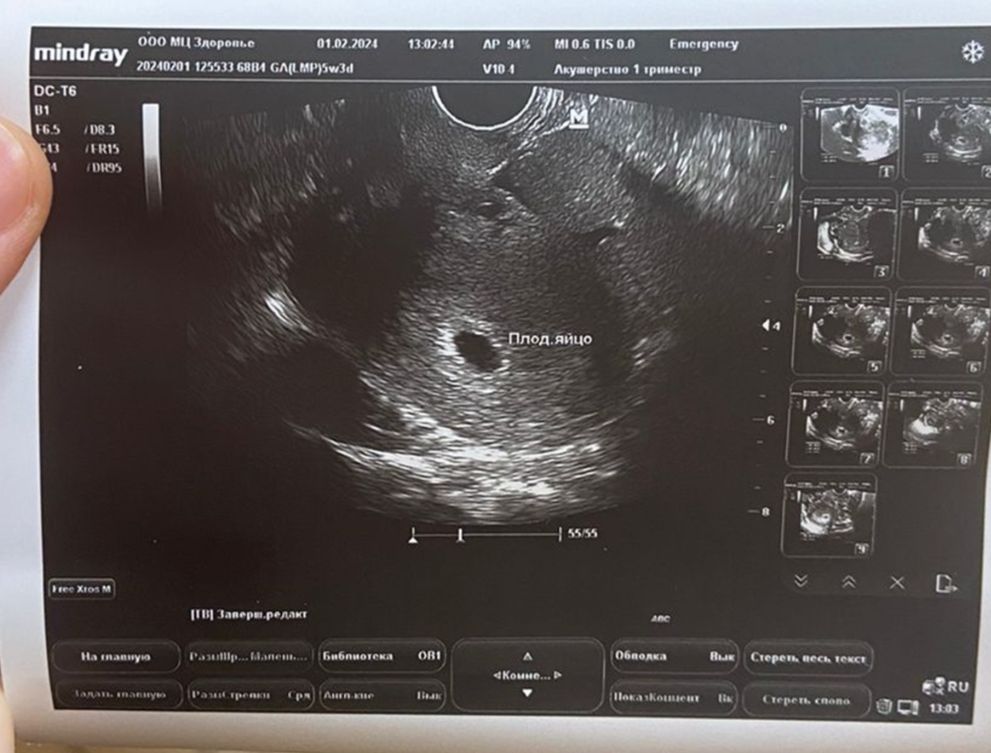

На узи на том же сроке увидели одно плодное яйцо. Гинеколог еще пошутил на тему того, что может образоваться второе. Помогите разобраться.